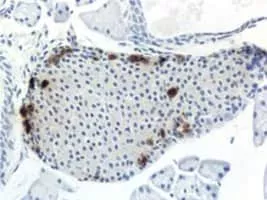

Pancreatic polypeptide photograph

Pancreatic polypeptide is a polypeptide secreted by PP cells in the endocrine pancreas predominantly in the head of the pancreas. It consists of 36 amino acids and has molecular weight about 4200 Da. The function of PP is to self-regulate pancreatic secretion activities.